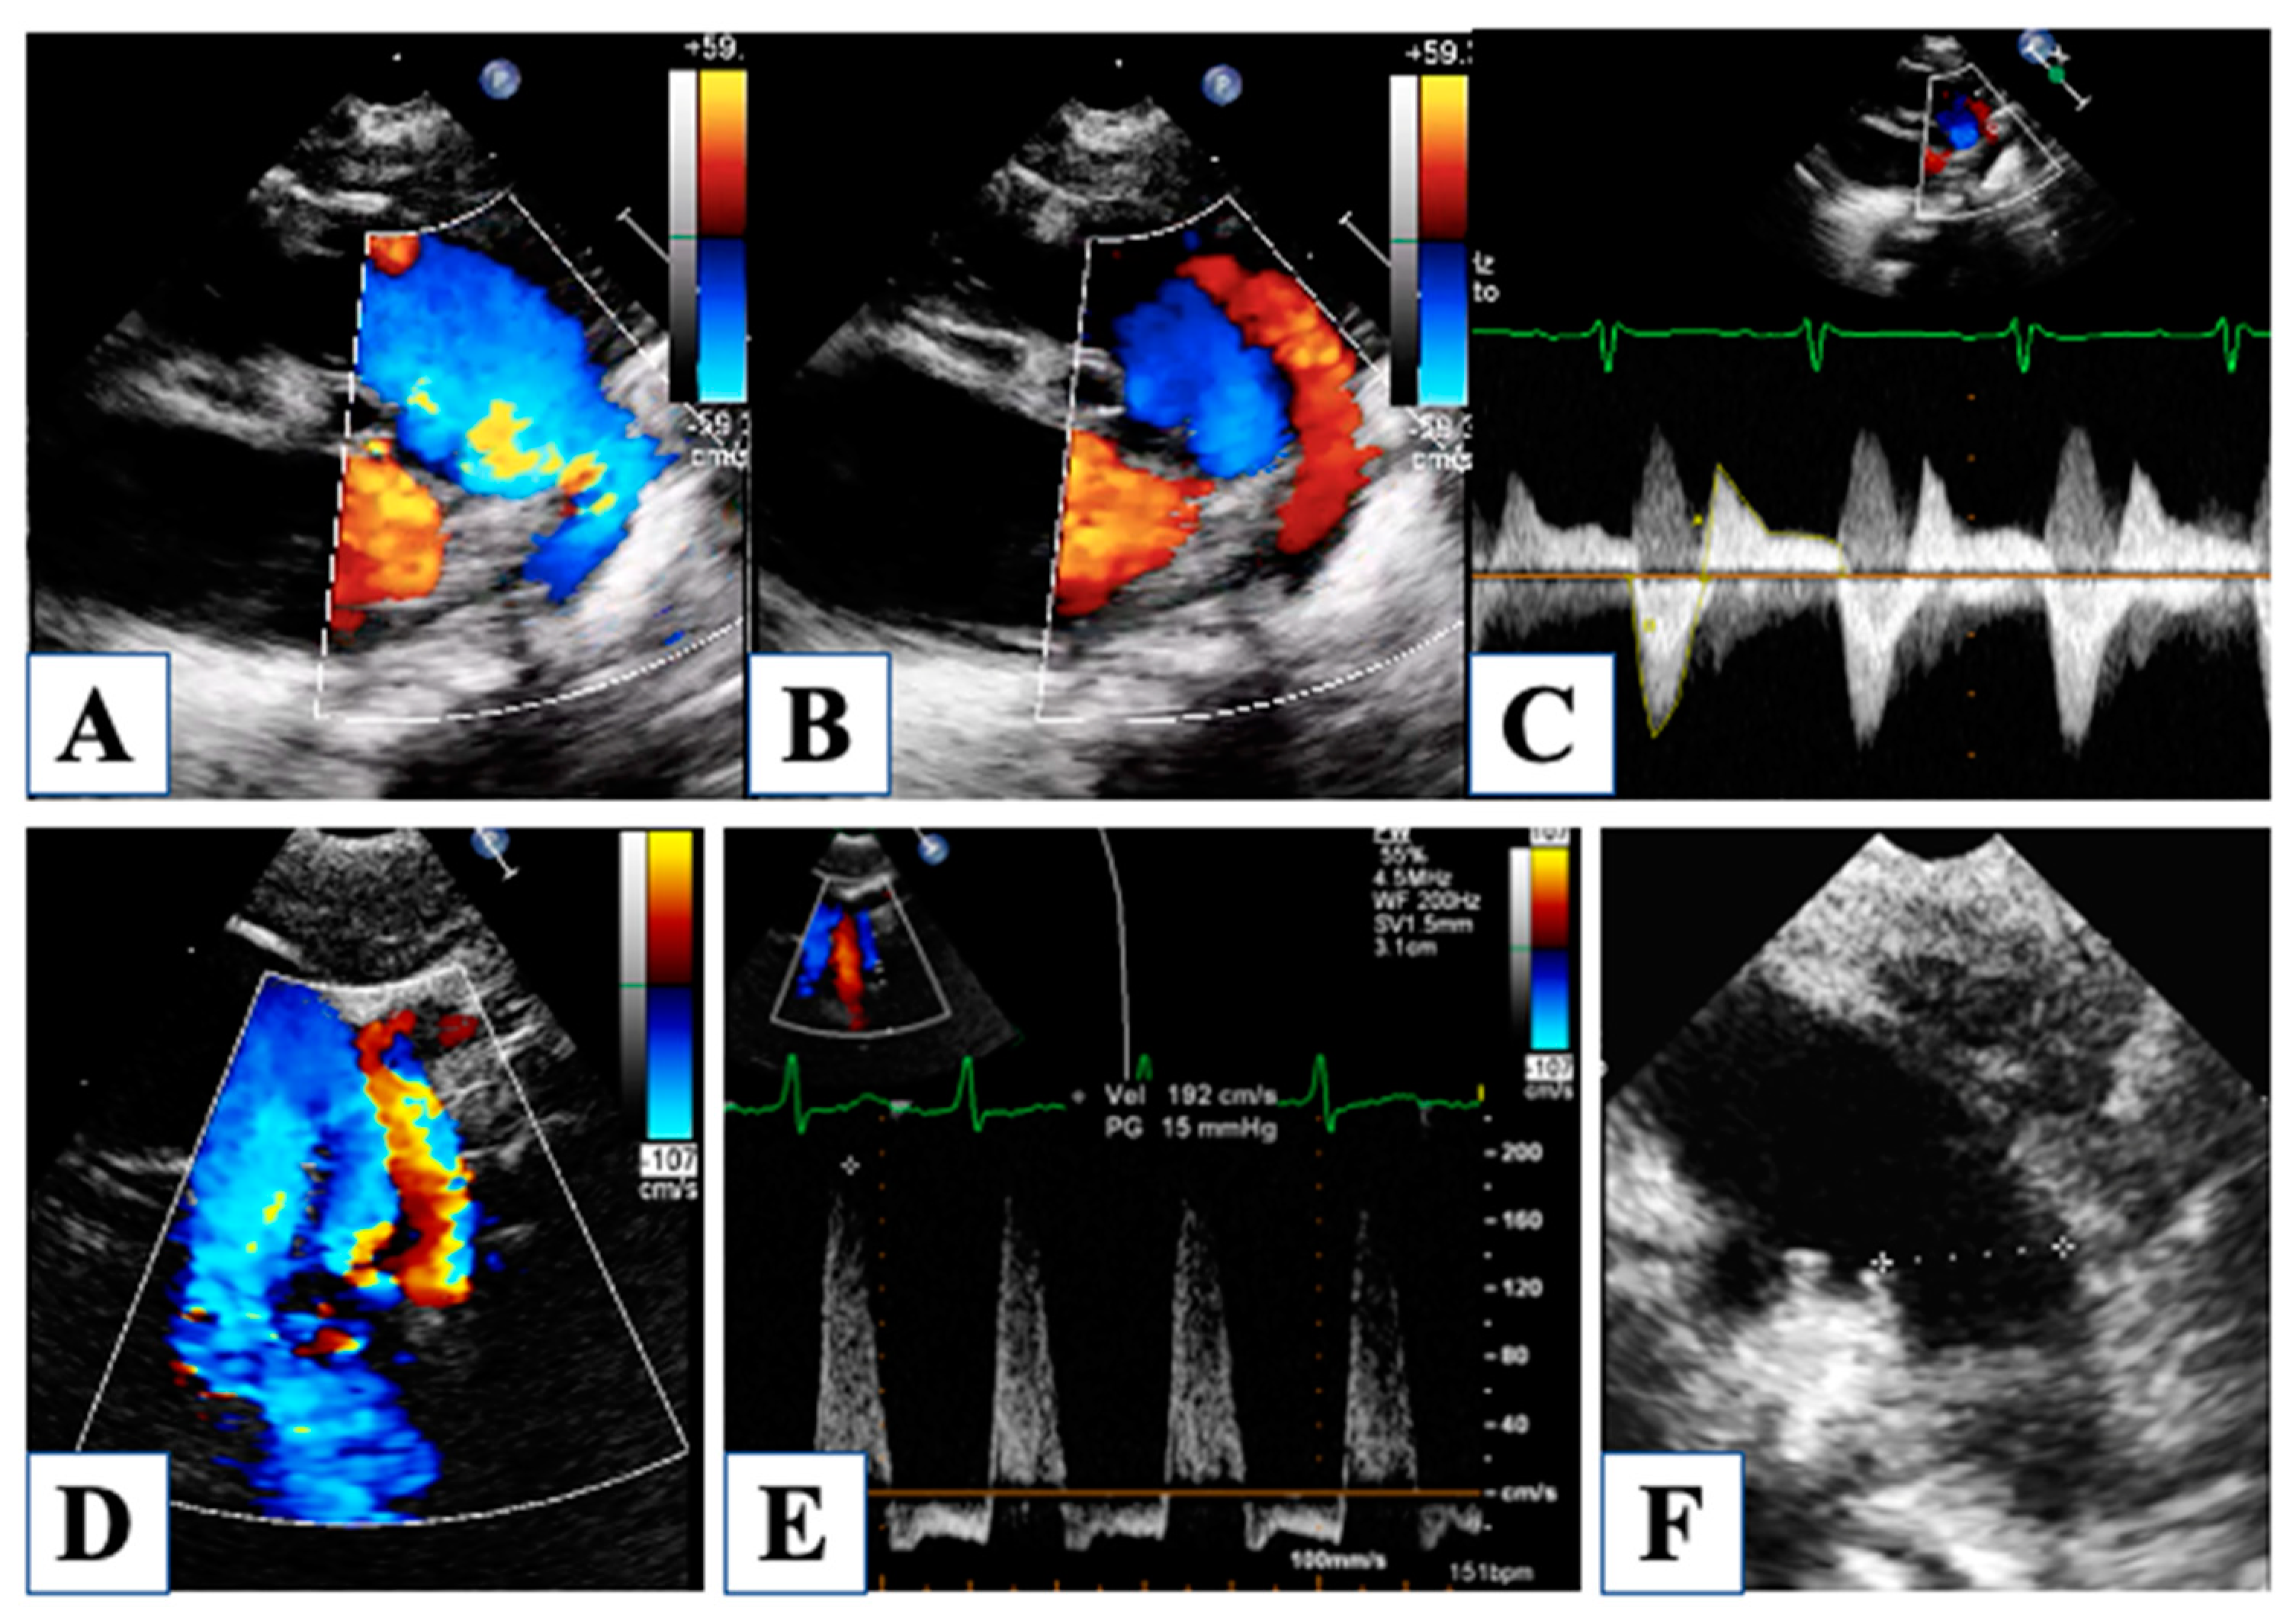

4. Morphological Insights: The Borderline LV

5. After Hybrid Procedure: The Interstage Period